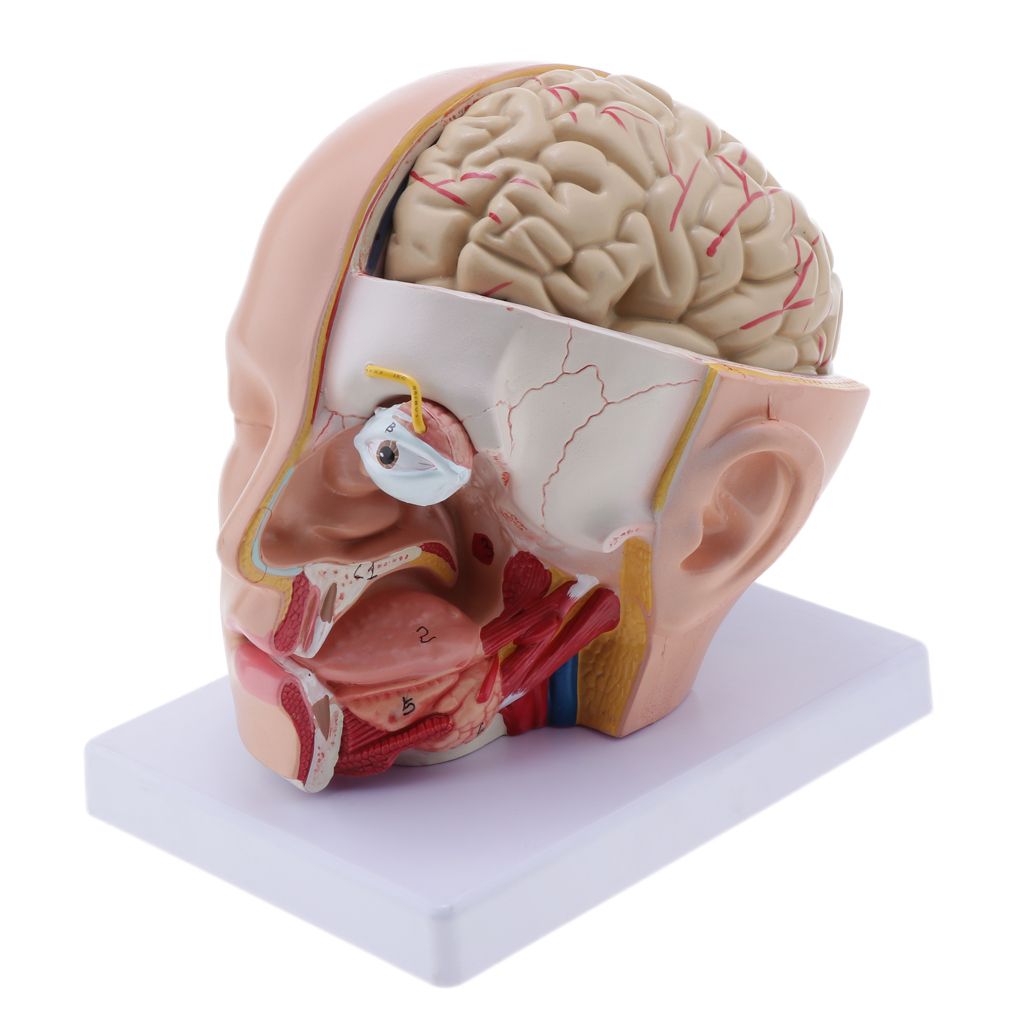

Анатомия Голова Картинки